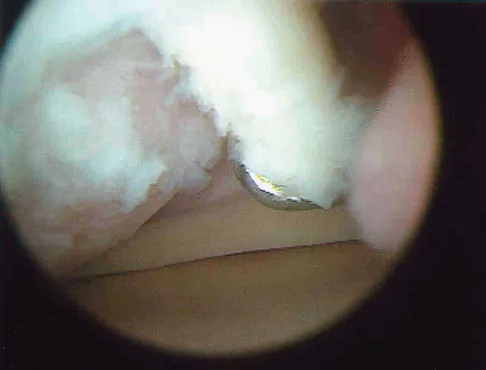

Question 523High Yield

What is the most frequent late complication of cementless fixation in total knee arthroplasty?

Explanation

The incidence of osteolysis, particularly around fixation screws in the tibia, can be as high as 30%. Stable femoral component fixation is generally maintained. Infection, subluxation of the patella, and stiffness can occur with either cemented or cementless fixation. Peters PC, Engh GA, Dwyer KA, Vinh TN: Osteolysis after total knee arthroplasty without cement. J Bone Joint Surg Am 1992;74:864-876.